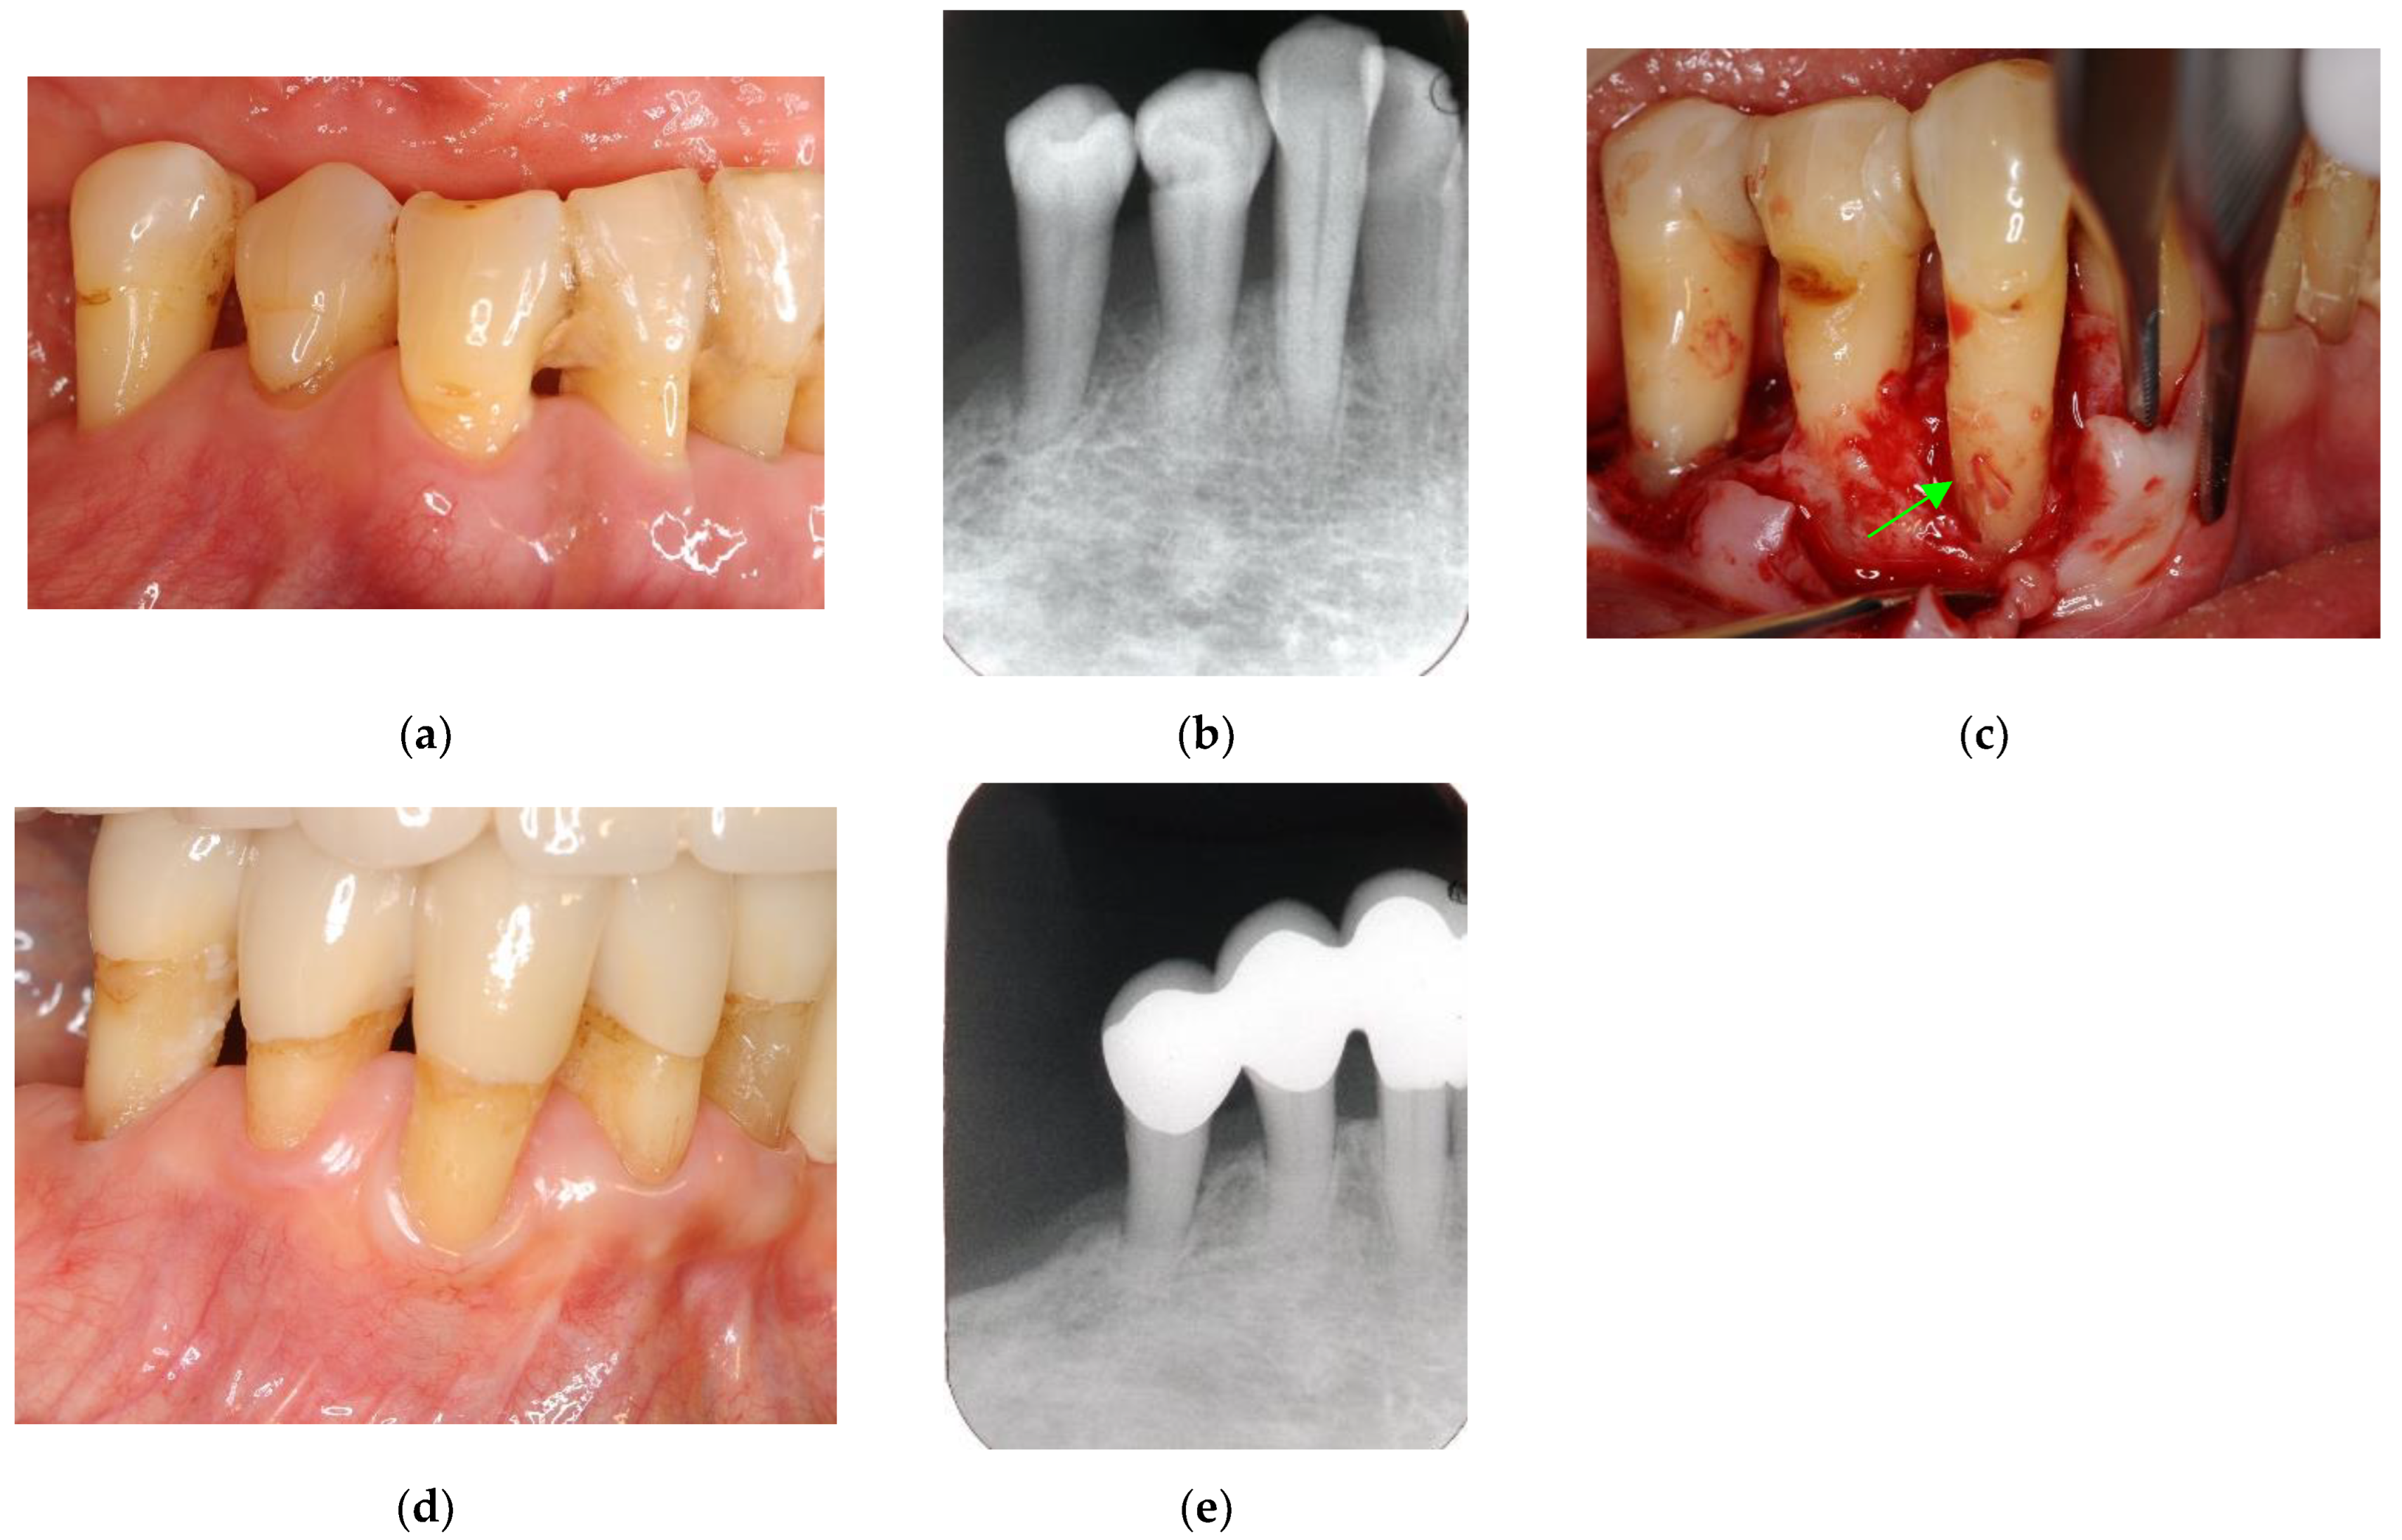

EPLs with a completely compromised periodontium can be defined as beyond treatment and treated by both periapical surgery and periodontal regenerative treatment with GTR of the membrane and/or biological medications, such as enamel matrix derivative or fibroblast growth factor-2 (Figure 7 and Figure 8). A tooth with EPL accompanied by severe periodontitis can be diagnosed as a high-risk or an untreatable tooth (Figure 8), as it includes combined endodontic and periodontal lesions. Predictable and successful treatment of these truly combined lesions, in which periodontal ligaments and cementum are affected by an inflammatory reaction, remains challenging even for specialists.

Figure 7. Clinical case 6. Male, age 58 yrs. (a) Preoperative periapical radiograph of the lower left incisor at baseline, showing the “bone” defect as a radiolucent area around the root. (b) Iatrogenic perforation during a previous dental procedure. (c) Postoperative periapical radiographs of the root canal treatment and a broken instrument. (d) Intraoral view 3 years after poor endodontic treatment, showing a fistula at the apical site of the tooth. (e,f) Flap retraction and debriding of the defect at both the labial and lingual sites, showing expansive bone resorption. (g) GTR treatment with resorbable membranes at both the labial and lingual sites. (h) Follow-up intraoral finding 10 years later, showing healthy gingiva. (i) Follow-up periapical radiograph 10 years after surgery. (j,k) Preoperative CBCT and follow-up CBCT after 10 years, showing periodontal tissue regeneration.

Figure 8. Clinical case 7. Male, age 54 yrs. (a,b) Periapical radiographs of the upper right second premolar and first molar at baseline, with the “bone” defect presenting as a radiolucent area around the root apex. In addition, deep pockets were present, and electric pulp tests were positive, suggesting retrograde pulpitis. (b) Periapical radiograph after root canal treatment. (c) Intraoral examination of the upper right molar before surgery (PD 9 mm). (d) View after flap retraction, debriding of the defects, and application of an enamel matrix derivative. (e) Final prosthesis 2 years later, presenting with healthy gingiva (PD < 3 mm). (f) Periapical radiograph 2 years later.